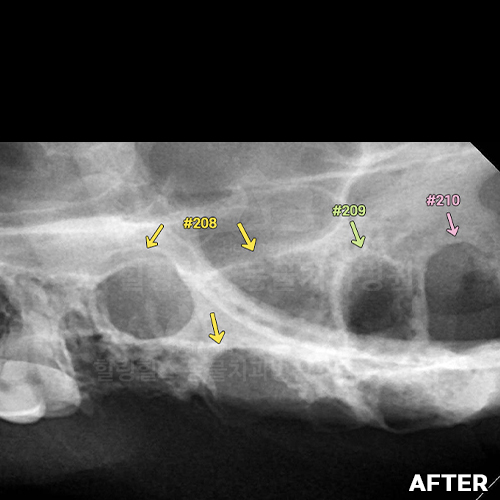

[1.7kg 초소형견 턱뼈에 금이 가게 하고 구멍을 내는 강아지치주염 - 안전발치]

샘플